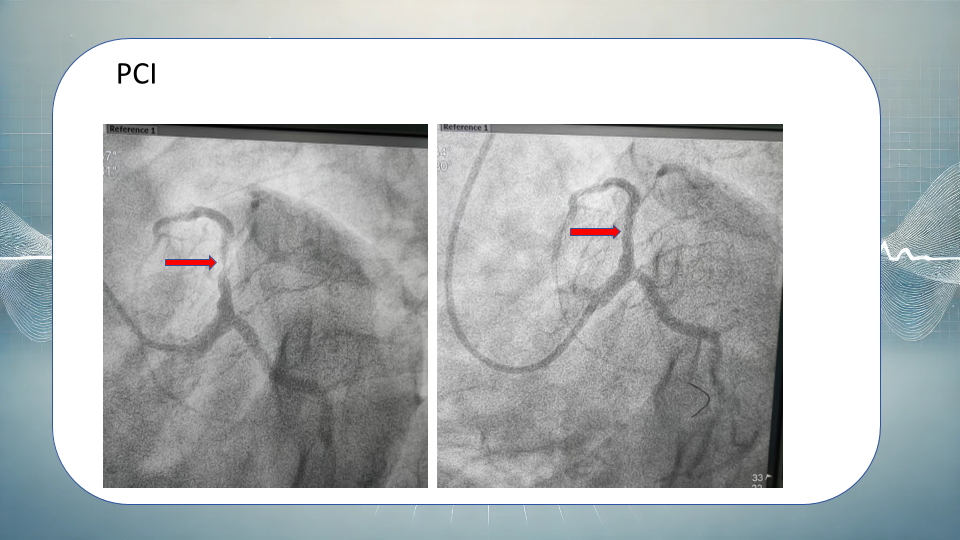

急性心梗健康宣教